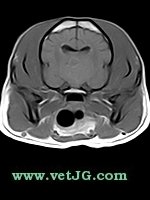

RESONANCIA MAGNÉTICA

TC

AXIAL